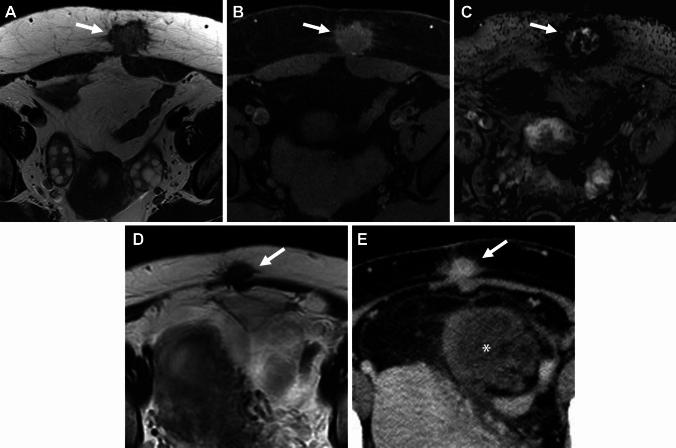

Endometriosis is a benign, common, but controversial disease due to its enigmatic etiopathogenesis and biological behavior. Recent studies suggest multiple genetic, and environmental factors may affect its onset and development. Genomic analysis revealed the presence of cancer-associated gene mutations, which may reflect the neoplastic aspect of endometriosis. The management has changed dramatically with the development of fertility-preserving, minimally invasive therapies. Diagnostic strategies based on these recent basic and clinical findings are reviewed. With a focus on the presentation of clinical cases, we discuss the imaging manifestations of endometriomas, deep endometriosis, less common site and rare site endometriosis, various complications, endometriosis-associated tumor-like lesions, and malignant transformation, with pathophysiologic conditions.